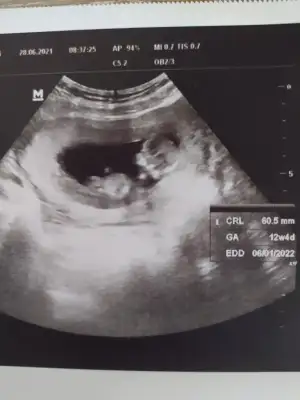

Selamlar herkese 😊 sabah doktora gittim baya büyümüş 🙈👶🏼 bes alti tup kan alindi hem kan testi hem ikili test icin bir de idrar tahlili istedi doktor. İnşallah güzel çıkacak sonuçlar 🙏

T tulperde rica etsem tahmin alabilir miyim cok arada kaldım 🙈 doktor bisey demedi

Eklentiler

• IMG_20210628_091147.webp

IMG_20210628_091147.webp

20,8 KB · Görüntüleme: 82